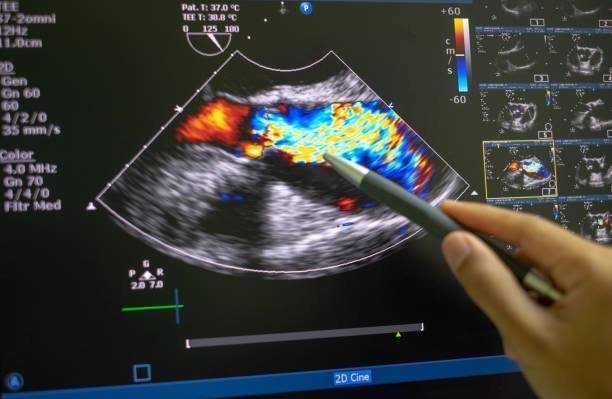

Color Doppler USG

The Color Doppler Ultrasound (USG) is a non-invasive imaging technique that evaluates blood flow in vessels and organs. It is widely used in pregnancy to monitor fetal health and in gynecology to assess conditions like ovarian torsion, varicose veins, or uterine abnormalities, ensuring accurate and timely diagnosis.